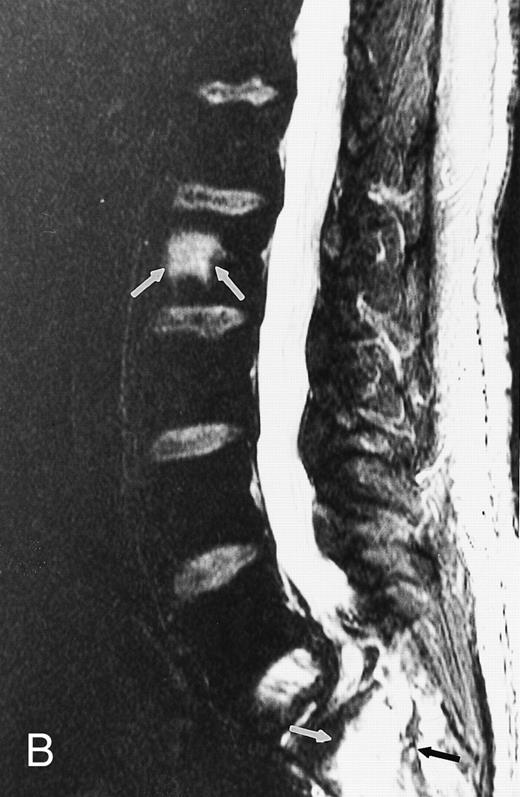

Focal MR pattern of abnormal marrow in a 48-year-old man with multiple myeloma: T1-weighted (500/10, TR/TE) (A), T2-weighted, fat-suppressed fast spin echo (5000/96, TR/TE, ET 16) (B), and enhanced T1-weighted (500/10, TR/TE) (C) sagittal MR images of the lumbar spine. Focal lesions (arrows) in L2 and S1 are dark in (A), bright in (B), and in (C) they enhance and become almost imperceptible from the uninvolved marrow.